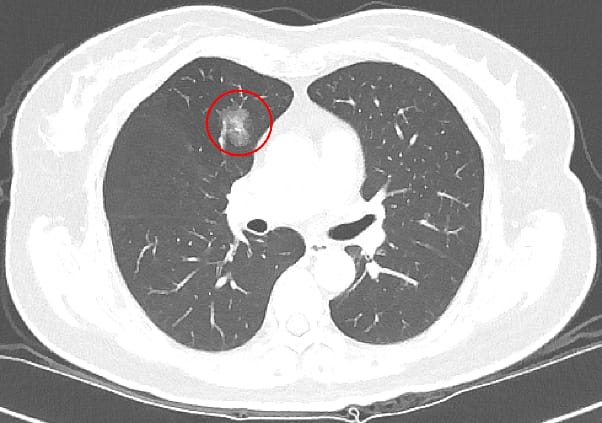

台北慈濟醫院肺癌篩檢研究|LDCT檢測準確率達67% 不抽菸者也需定期檢查